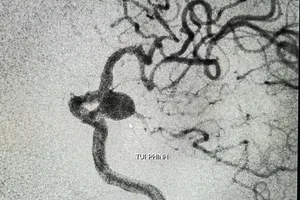

TP Cần Thơ: Can thiệp thành công túi phình mạch não lớn cho cụ bà 90 tuổi Y tế - Sức khỏe 04/09/2025 16:39